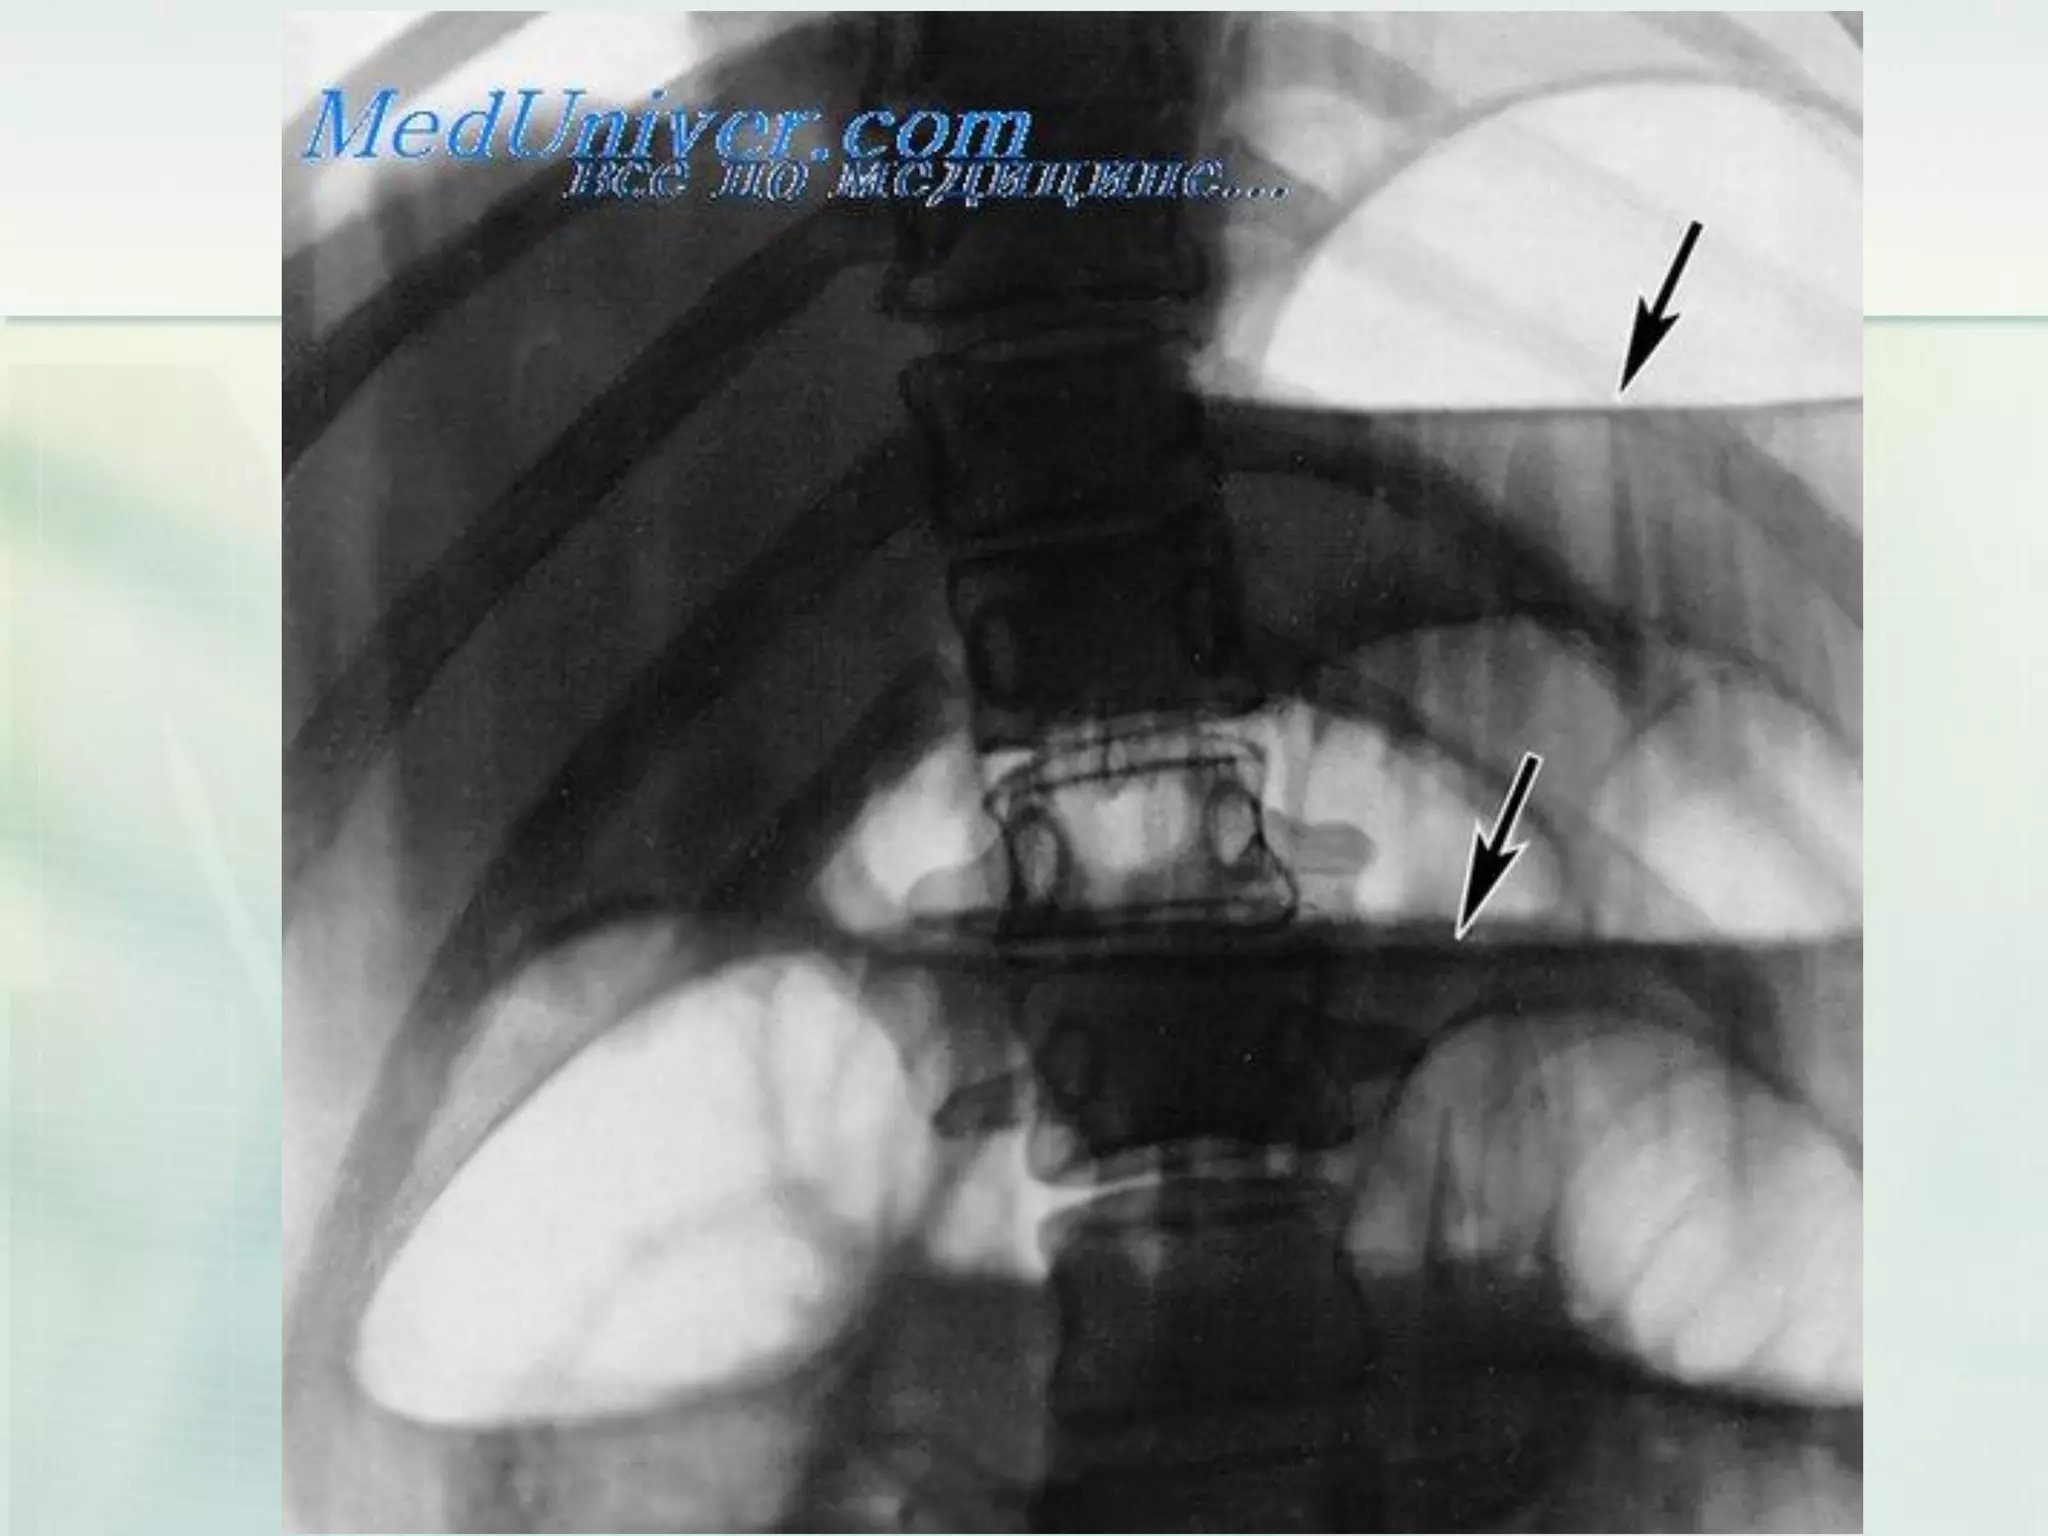

 Barium are administered with timed plain

films to evaluate intraluminal transit.

 This study can show the point of obstruction,

the degree of narrowing in the case of a

partial small bowel obstruction, and

associated mucosal abnormalities.

 It involves an initial bolus of enteral contrast

with subsequent filming to document transit

through the small bowel to the colon.

 When contrast does not reach the colon after

several hours, a complete obstruction must

be postulated.

Laboratory investigations (Small bowelobstruction)  Barium are administered with timed plain films to evaluate intraluminal transit.  This study can show the point of obstruction, the degree of narrowing in the case of a partial small bowel obstruction, and associated mucosal abnormalities.  It involves an initial bolus of enteral contrast with subsequent filming to document transit through the small bowel to the colon.  When contrast does not reach the colon after several hours, a complete obstruction must be postulated.